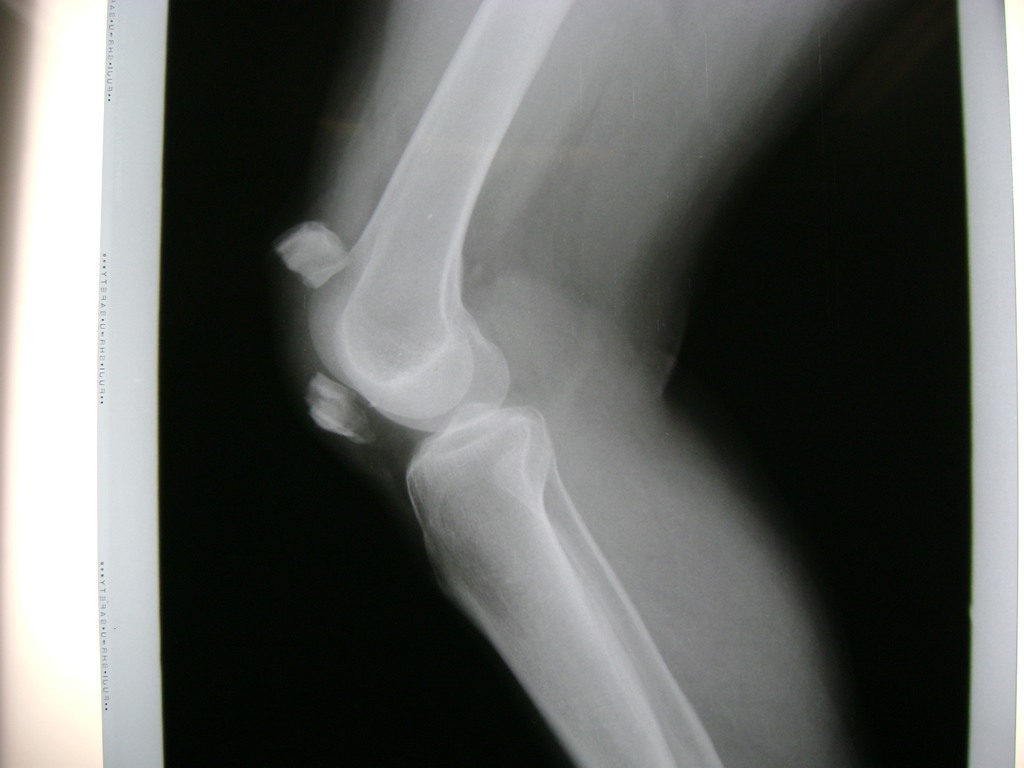

La artroscopia de rodilla es un cirugía en el cual la estructura interna de la articulación es examinada ya sea para realizar un diagnostico o para realizar un tratamiento, este procedimiento se realiza utilizando un instrumento parecido a un pequeño tubo llamado artroscopio.

La artroscopia se popularizo en 1960 y hoy en día es muy común en todo el mundo. Típicamente, es realizada por cirujanos ortopédicos de manera ambulatoria. Cuando se realiza de manera ambulatoria los pacientes pueden regresar a casa después de la operación, no se requiere quedarse en hospital.